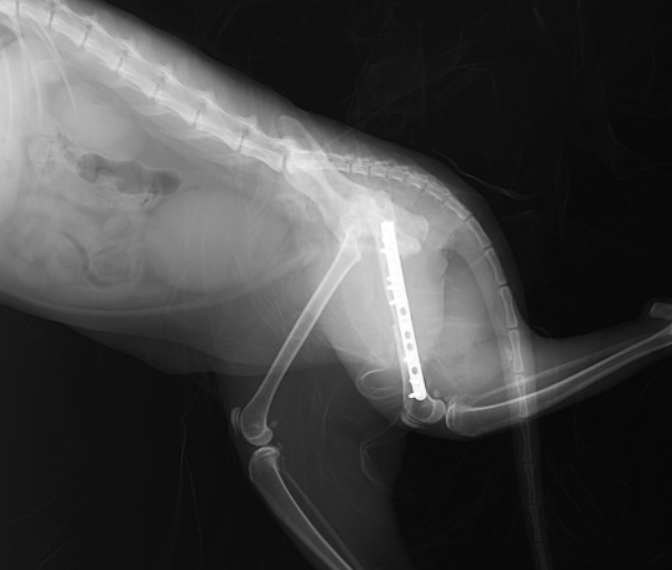

左大腿骨(後ろ足の骨)の粉砕骨折の事例です。外に出る子だったので、交通事故に遭われたのだと思います。

手術を実施し、プレートとボルトを用いて骨折整復手術を行いました。

2. 骨の固定:骨折部位を固定するためにギプス、プレートやピンを用いて損傷した骨の整復・固定する外科手術が用いられることがあります。